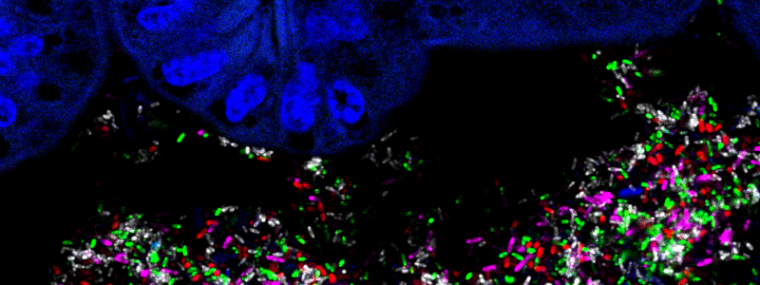

The scope of GCIR transcends ‘beyond’ pathogens; it delves into the complex microbial flora that resides within us: the microbiome. Understanding the delicate symbiosis between us and the ‘healthy’ micro-organisms in our gut, respiratory tract, genital tract or skin is crucial, as it influences our immune response and, if imbalanced, promotes autoinflammatory processes.